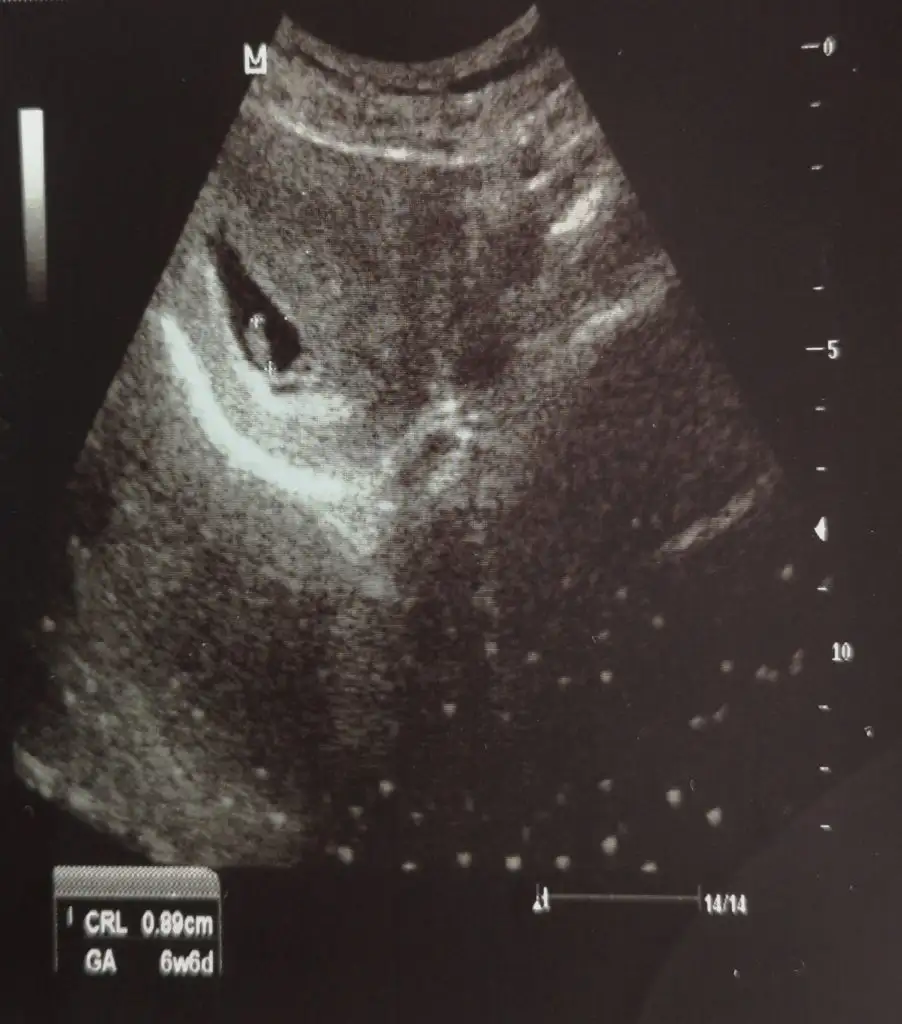

Kız buna göre tabi en iyi 11 12 13 haftalar olmalıIkra meyra canım merhaba 6+6daki karından usgmiz bakabilir misin? Allah herkese sağlıklı akıllı bebisler nasip etsin elbet isteğimiz bu ama insan merak ediyor yani

Kız gibi sanki. Başka USG varsa paylaşın emin olamadım

Burada net değil

Burada net değil12 13 olursa paylaşın kaç haftalık USG ler